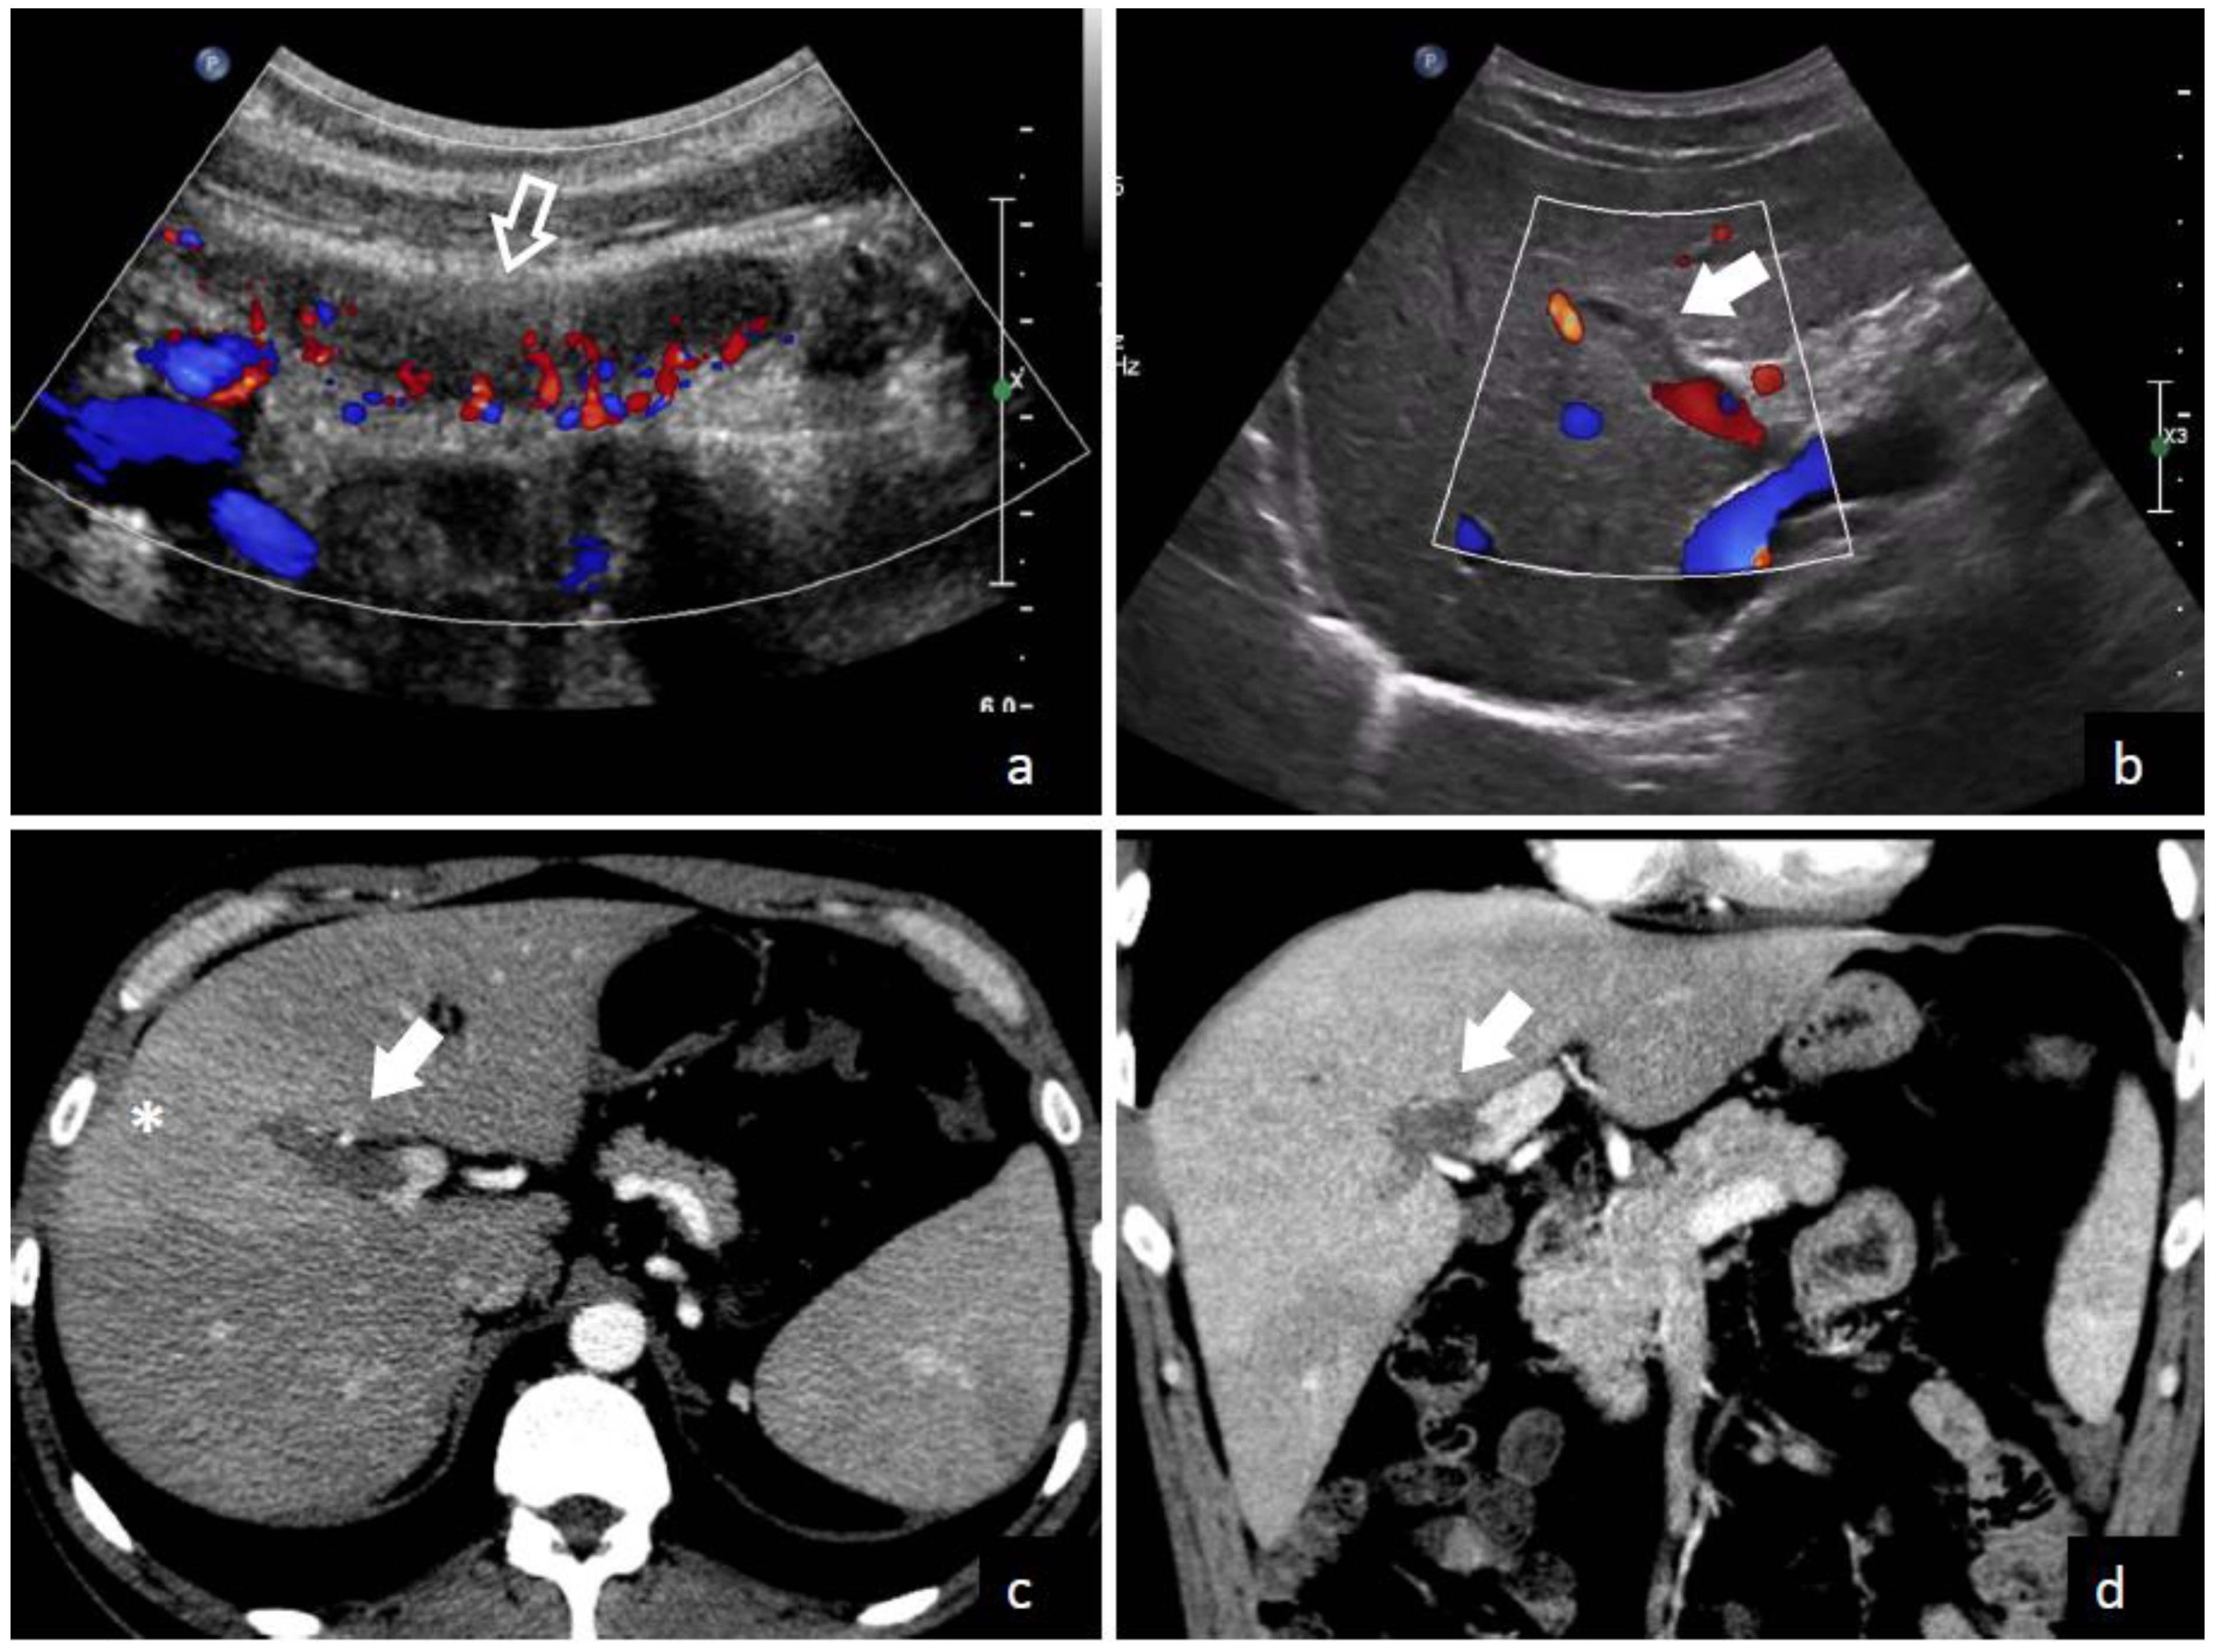

4.2. Imaging Studies